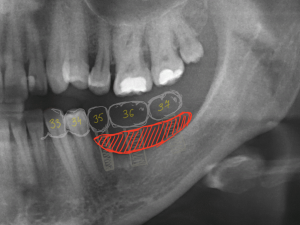

Почему стоит удалять зубы мудрости, даже если они не беспокоят? Кисты, биоматериалы и хирургия

Примерно полтора года назад к нам в клинику обратилась молодая и красивая девушка. Все бы ничего, ничто ее не беспокоило, но вот однажды пошла она лечить зубки, и ей сделали панорамный снимок. Сделали панорамный снимок — забегали, заохали, послали на компьютерную томографию.